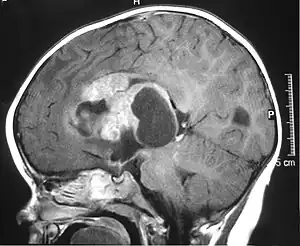

| MRI of an AT/RT | |

Appearance on radiologic exam

AT/RTs can occur at any sites within the CNS; however, about 60% are located in the posterior fossa or cerebellar area. The ASCO study showed 52% posterior fossa; 39% sPNET; 5% pineal; 2% spinal, and 2% multifocal.[1]

The tumors' appearance on CT and MRI are not specific, tending towards large size, calcifications, necrosis (tissue death), and hemorrhage (bleeding). Radiological studies alone cannot identify AT/RT; a pathologist almost always has to evaluate a brain tissue sample.

The increased cellularity of the tumor may make the appearance on an uncontrasted CT to have increased attenuation. Solid parts of the tumor often enhance with contrast MRI finding on T1 and T2 weighted images are variable. Precontrast T2 weighted images may show an isosignal or slightly hypersignal. Solid components of the tumor may enhance with contrast, but not always. MRI studies appear to be more able to pick up metastatic foci in other intracranial locations, as well as intraspinal locations.

Preoperative and follow-up studies are needed to detect metastatic disease.